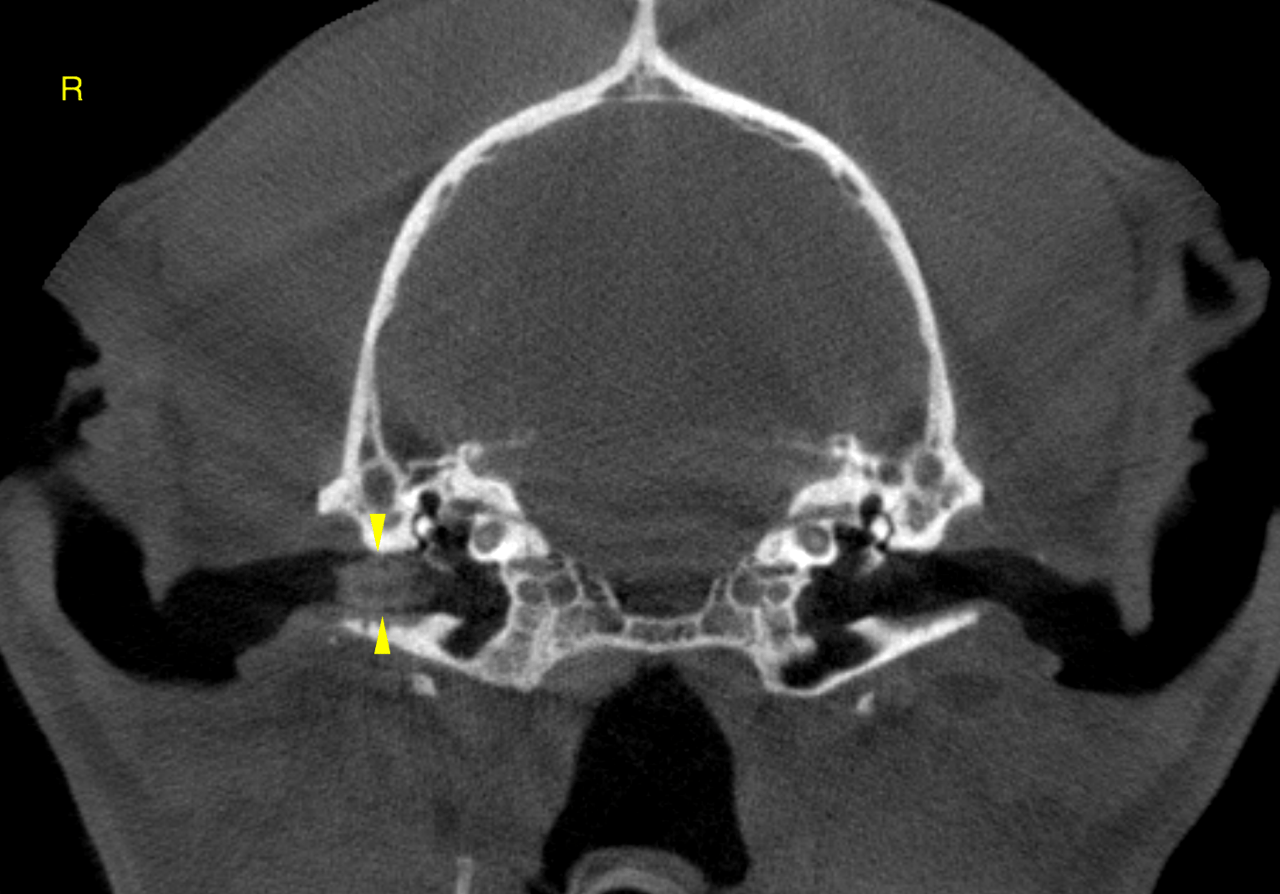

CT of the head, plain – The computed tomography reveals a moderate and mild amount of uniformly soft

tissue attenuating material in the dependent portion of the left and right nasal cavity

respectively. Part of the material is demarcated by a meniscus sign (horizontal viscous

fluid gas interface).

A mild amount of soft tissue attenuating material is noted medially within the right

external ear canal next to the entrance into the tympanic bulla. The tympanic bulla

itself is within normal limits.